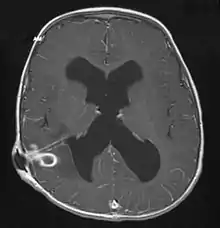

| Brain abscess in a person with a CSF shunt.[1] | |